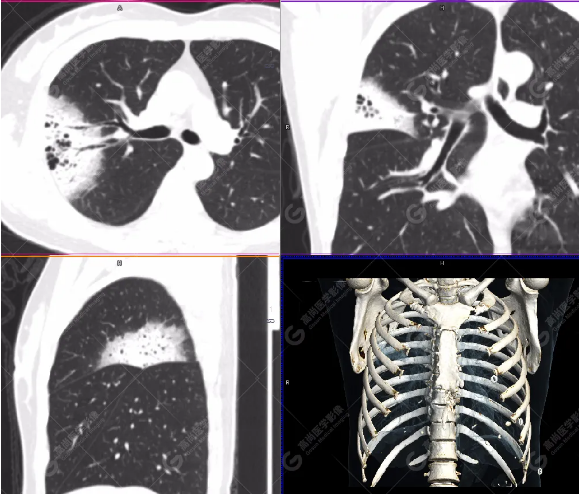

右肺上葉斑片狀高密度影,部分實變,邊界清楚,未跨葉間裂;內(nèi)空氣支氣管征、蟲蝕樣空洞、周圍暈征;放射性攝取增高,SUVmax=4.1。

右肺上葉后段胸膜下片塊狀高代謝病灶,考慮為肺淋巴瘤,請結(jié)合臨床病理。病理報告

右肺上葉穿刺活檢:肺淋巴瘤,傾向黏膜相關(guān)淋巴組織邊緣區(qū)淋巴瘤。